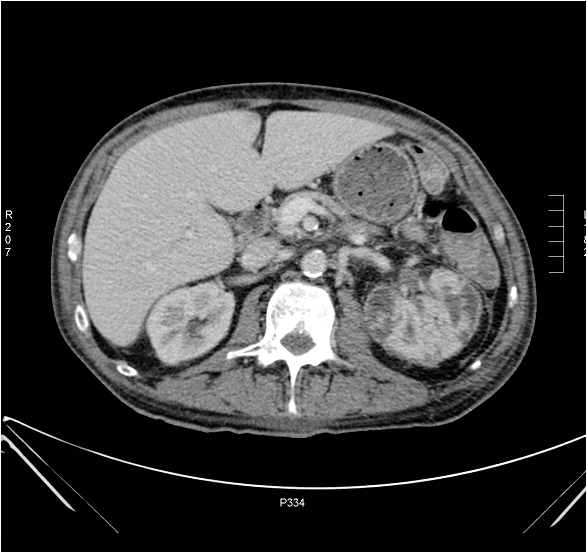

Image

Figure 2. Extensive right sided kidney tumor on CT

Diagnostics:with advancement of the cross-sectional imaging techniques multi-phase contrast enhanced CT became the basic diagnostic modality if a renal neoplasia is suspected.

The parenchymal lesion is revealed by its characteristic inhomogeneous contrast enhancement pattern and in certain cases by the presence of focal calcifications. CT has much better sensitivity than intravenous pyelogram, which has been extensively used in earlier times.

A properly preformed CT scan can be also considered a staging examination as it could reveal distant metastases and vascular invasion. Additional advantages of CT imaging can be attributed to the various digital elements and post processing features. Multi-plane reconstructions are available and auxiliary 3D or virtual urographic images can also be generated anytime from the primary dataset.